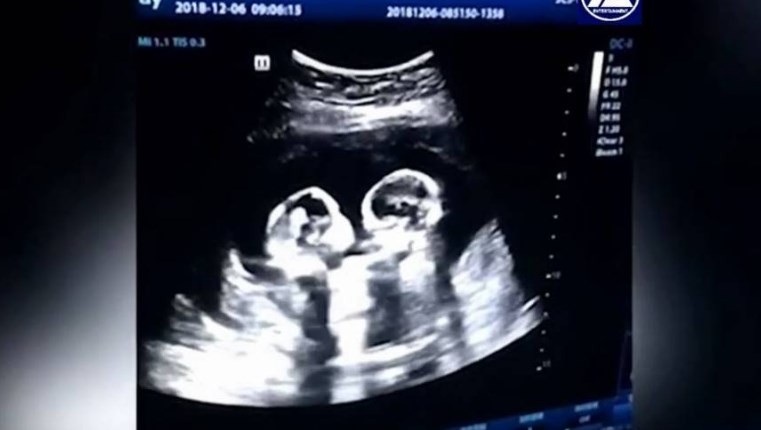

Video: la pelea entre gemelas en el útero de su madre

Un video de unas gemelas peleando dentro del útero de su madre se volvió viral.

El hecho ocurrió en China durante un control de rutina a los cuatro meses de gestación. La escena de las niñas que parecían estar luchando, llamó tanto la atención del padre que las grabó y luego subió a internet donde acumula más de 2,5 millones de reproducciones.

Las pequeñas que fueron llamadas Cherry y Strawberry, también habían sido captadas por su padre abrazadas en otra ecografía.